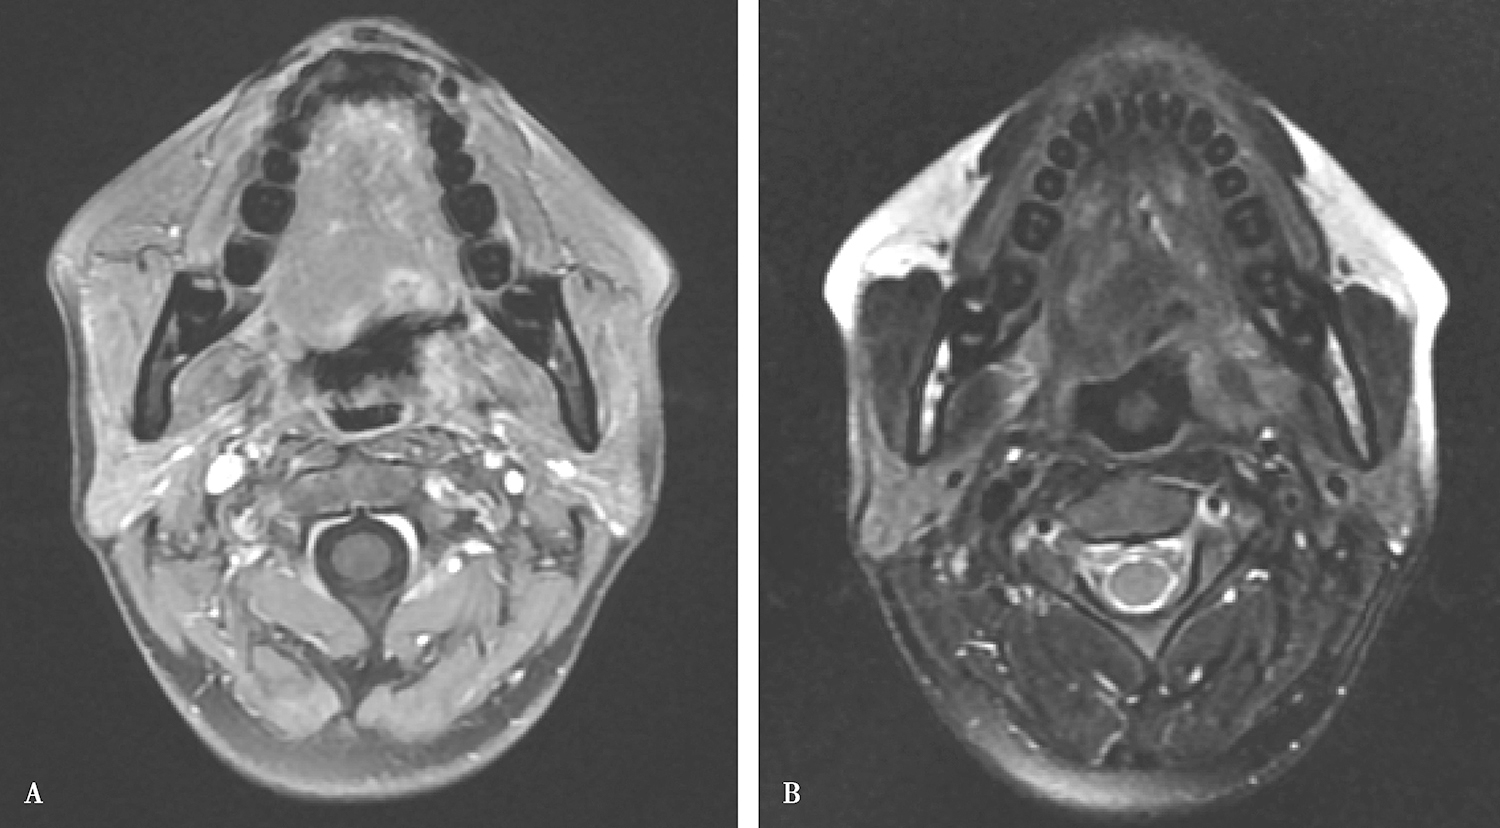

3.2011年12月28日口咽MR平扫检查

舌根部肿物,向前侵犯口底,大小约2.3cm×2.5cm×2.5cm,分叶状,边界不清楚,T1低信号,T2等信号,增强扫描不均匀环形强化(图2)。口咽左侧壁少许片状强化影,考虑为舌癌,病变可疑侵犯口咽左侧壁,请结合镜检;扫描范围内双侧颈部未见明确肿大淋巴结;喉部未见明确异常。

图2口腔MRI平扫示舌根部肿物向前侵犯口底A.MRI T2;B.MRI T1